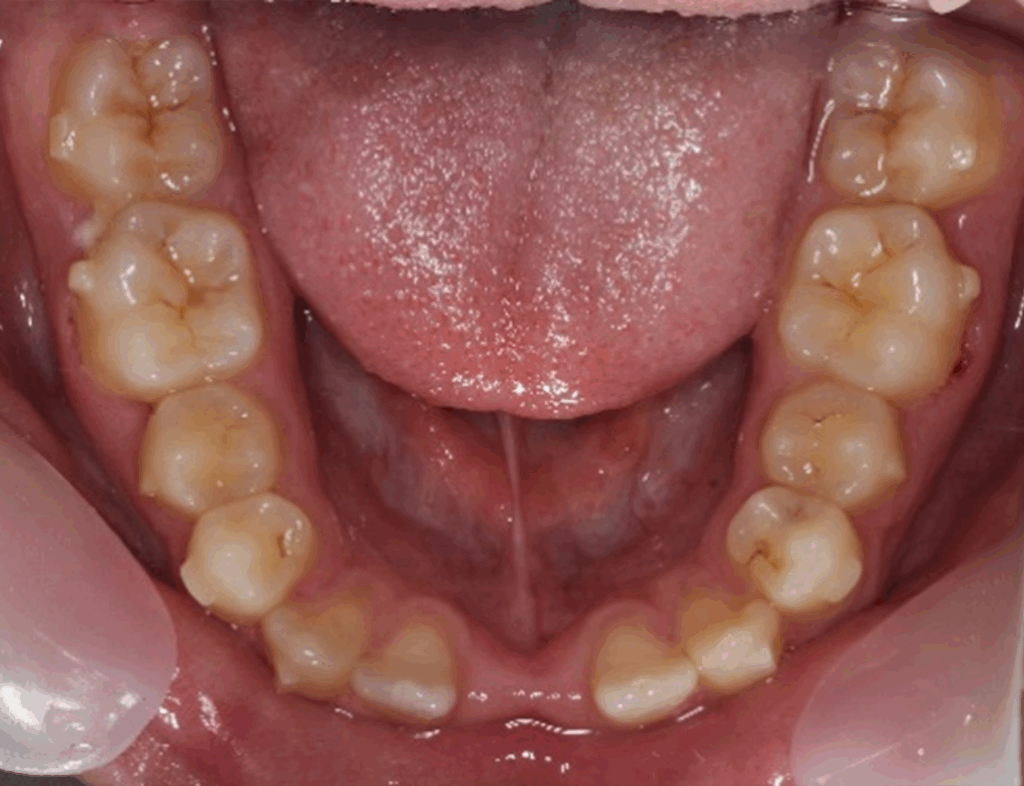

Skeletal Class II due to mandibular retrognathia, proclination of maxillary incisors, narrow arch creating a V-shaped arch, agenesis of 12, 31, 41, hyperdivergent facial pattern, moderate deep bite (2 mm), increased overjet (9 mm), asymmetric canine and molar Class II due to mandibular deviation to the left, maxillary midline deviation related to agenesis of 12, distal rotation of 35 and 45, and pronounced lower curve of Spee.

Lower arch: 31 active aligners

Incisor intrusion using frog staging

Vertical attachments on lower incisors for improved tipping control

Space opening for 31 and 41